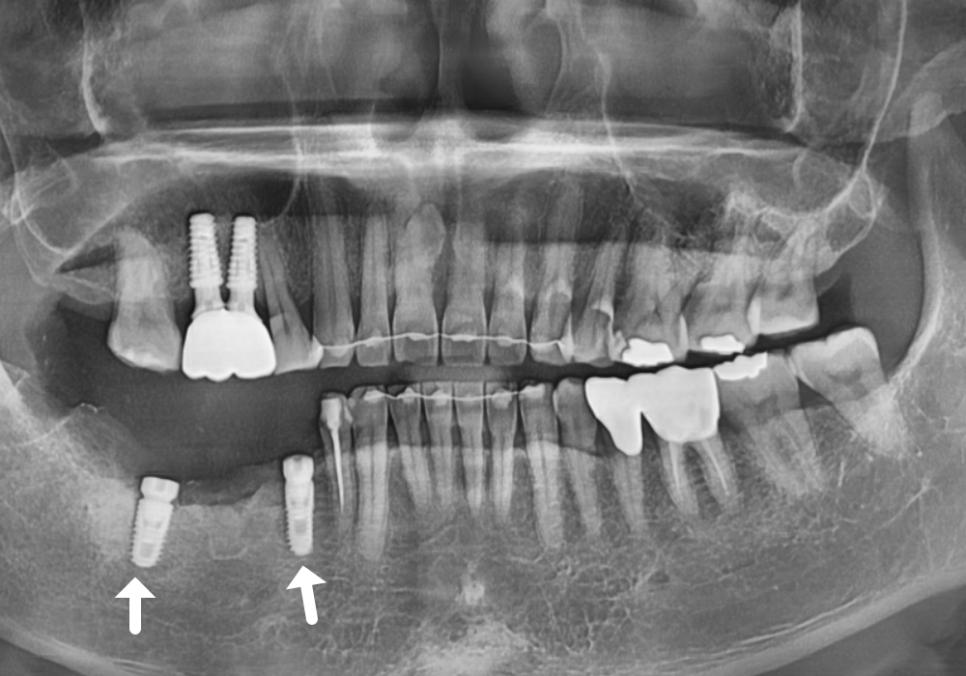

여기서 저는 환자분의 비용

부담을 줄여드리기 위해

양 끝에 2개의 임플란트 기둥만 튼튼하게 심고,

그 사이를 보철로 연결하는 방식을

제안해 드렸습니다.

치아를 3개 뽑았다고 해서

임플란트를 꼭 3개 다 심어야 하는 건 아니거든요~

불필요한 뼈이식도 막기 위해

CT를 꼼꼼히 분석했고,

꼭 필요한 부분(#47)에만 뼈이식을

동반해 안전하게 식립을 마쳤습니다.

260105